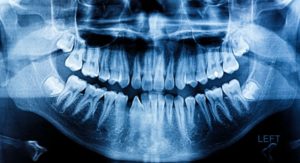

Do I Really Need X-Rays?

In the past, there has been a stigma around dental X-rays that often elicits questions from patients such as: Are X-rays really necessary? What can they show you? How often do I need them? Are they safe? In today’s blog, your dentist in Ft. Lauderdale takes the time to answer all of your questions about dental X-rays so you can understand how they might benefit you.